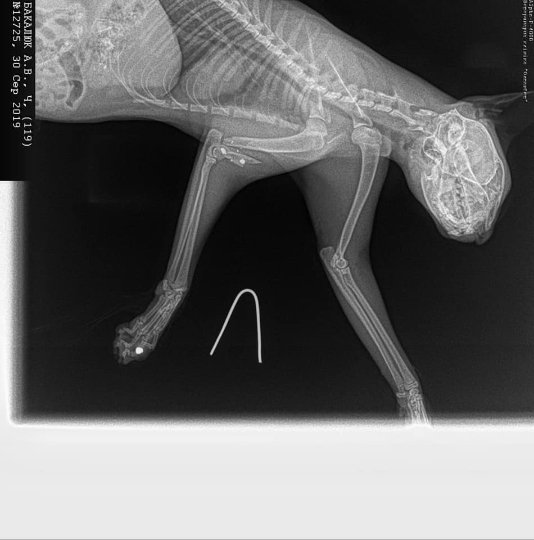

Неподалік Луцька невідомі стріляли у кота. ФОТО 18+

У селі Озерце невідомі кілька разів поцілили у кота.

Окрім того, автор допису оприлюднив фотографії кота після хіхругічного втручання і написав, що тварині потрібно зробити ще дві операції.